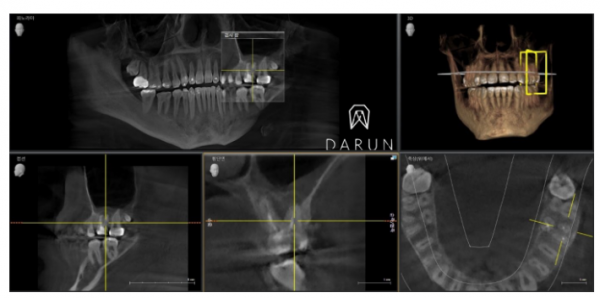

CT 사진입니다.

표시한 이부분이 전부다 염증이에요..

뿌리사이에 저렇게 광범위하게 진행된 것 같아요.

저렇게 까지 악화된 경우엔 예후가 안 좋을 수 있어요..